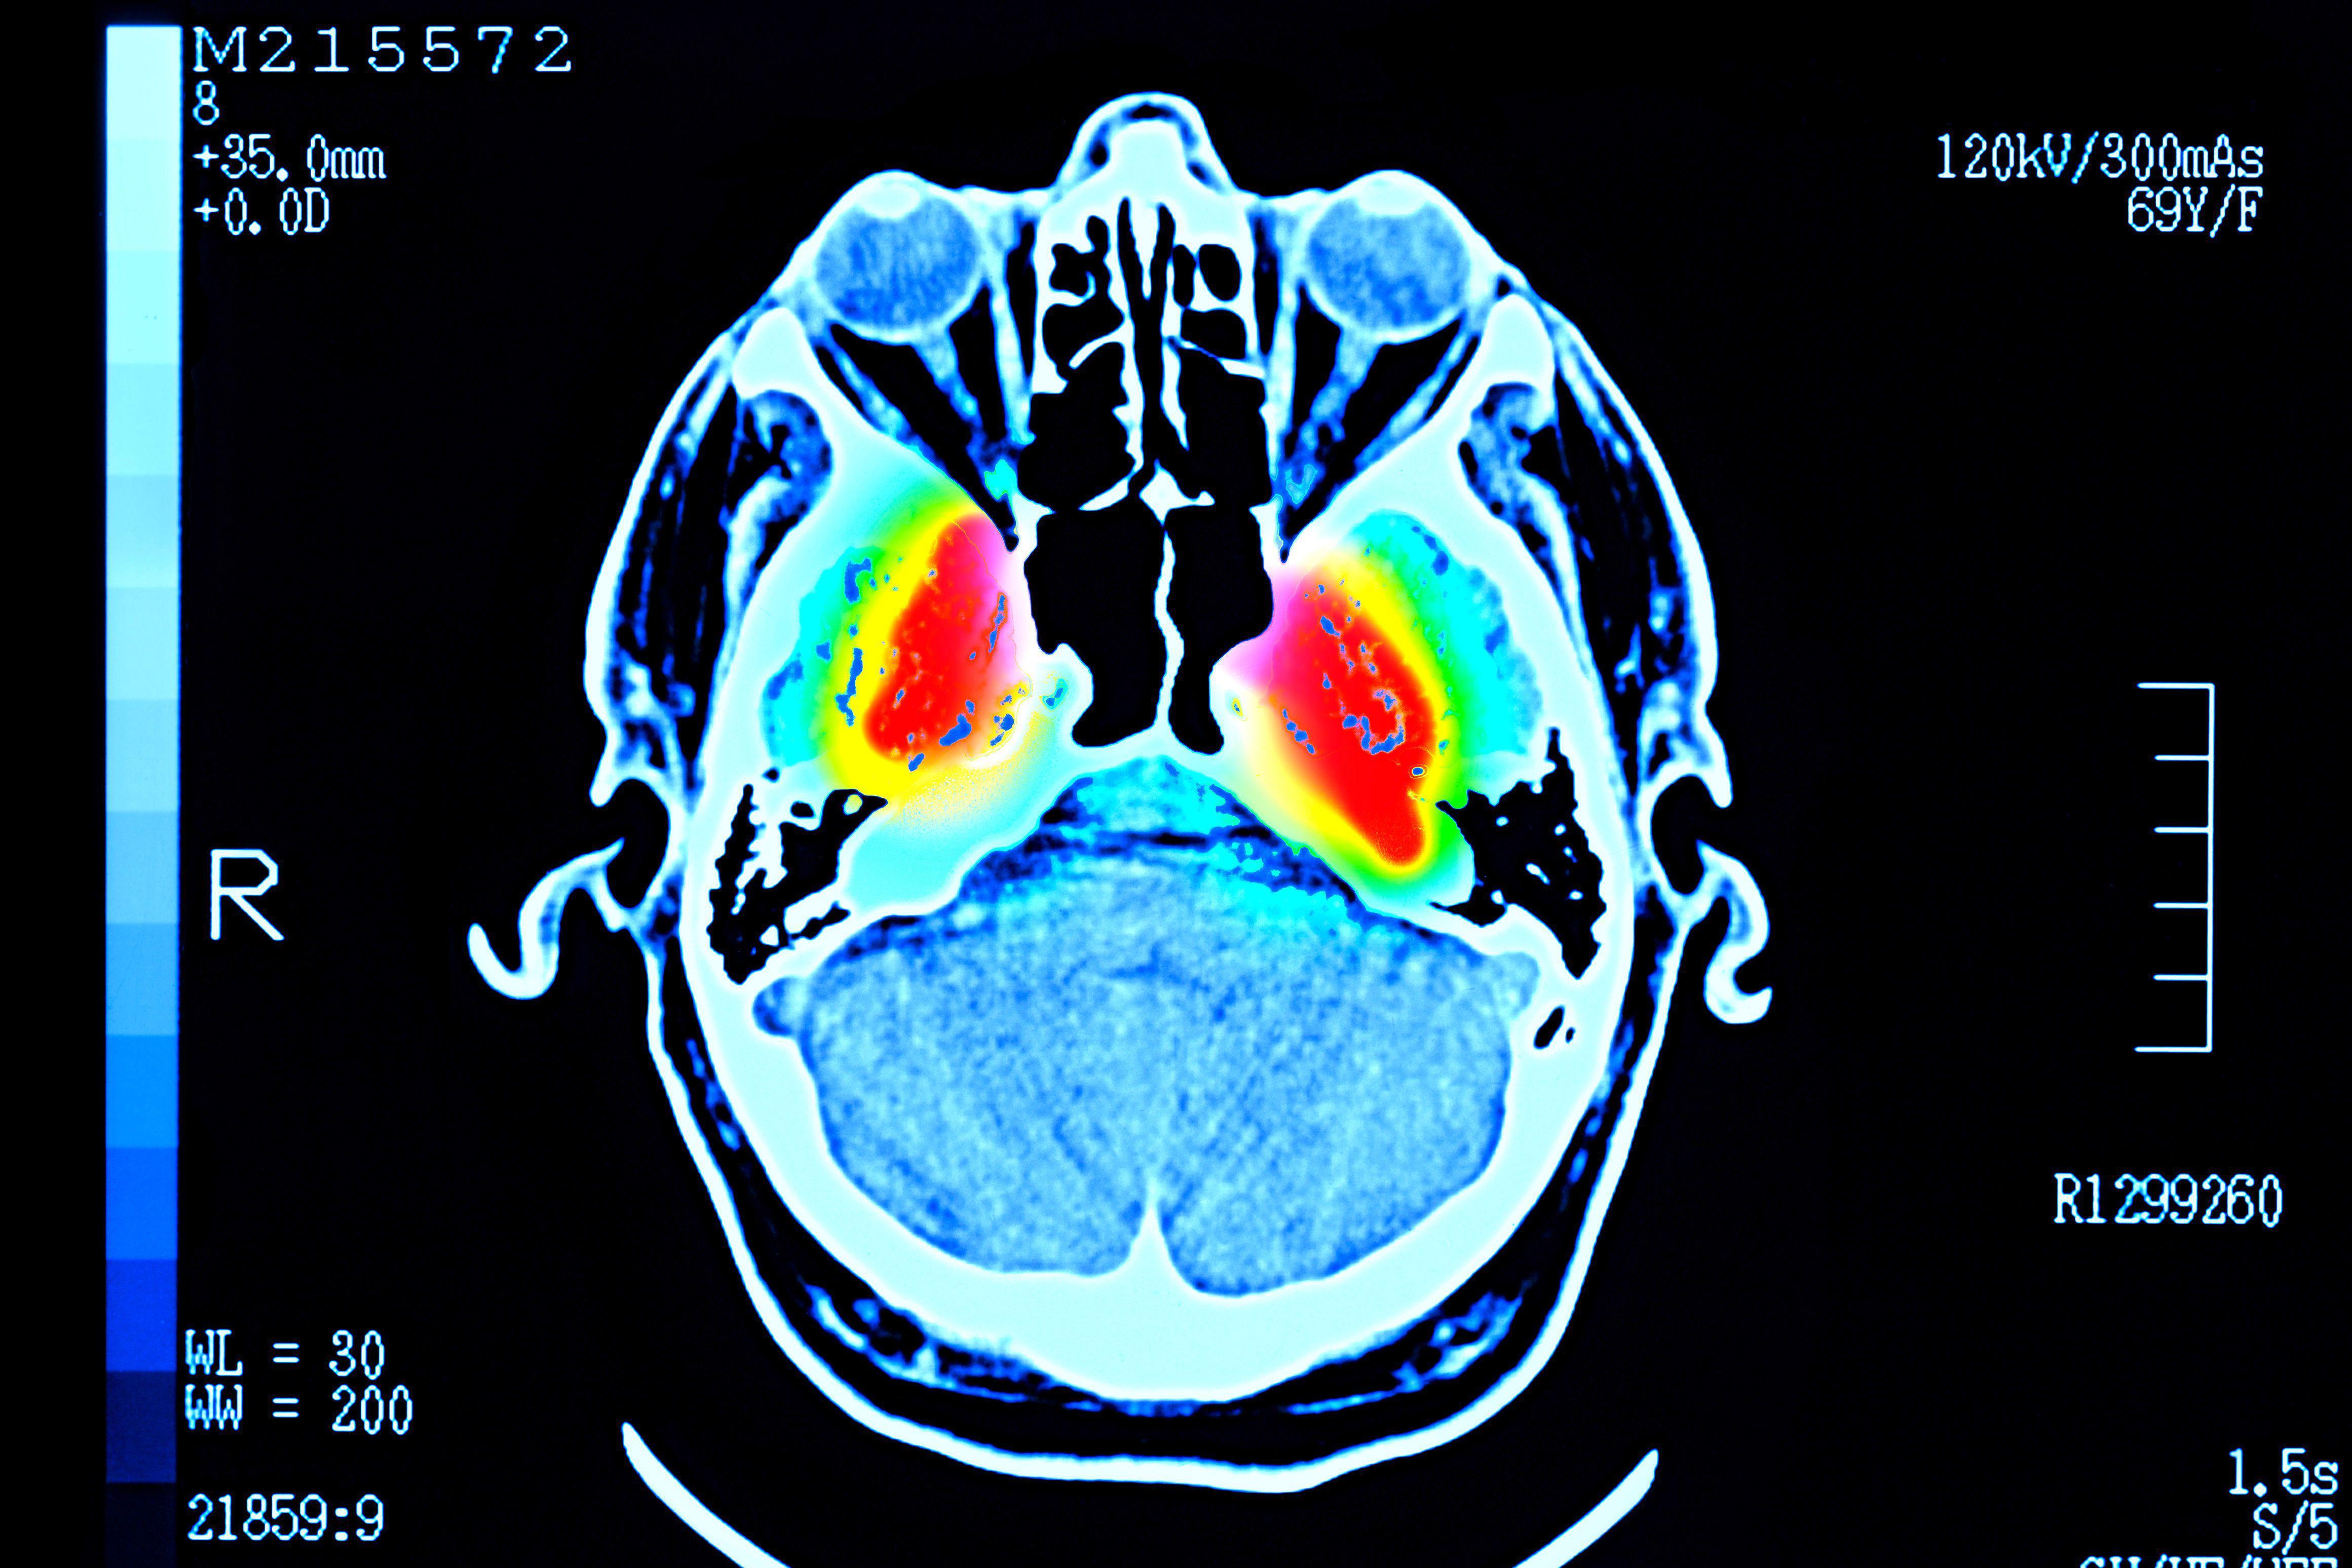

Skeniranje ljudskog mozga prikazuje crvene oblasti oko centra, okružene žutim, zelenim i svetloplavim oblastima

Getty Images

Istraživači kažu da njihovi nalazi mogu da pomognu da bolje razumemo kako se rizik od poremećaja mentalnog zdravlja i demencije menja tokom života